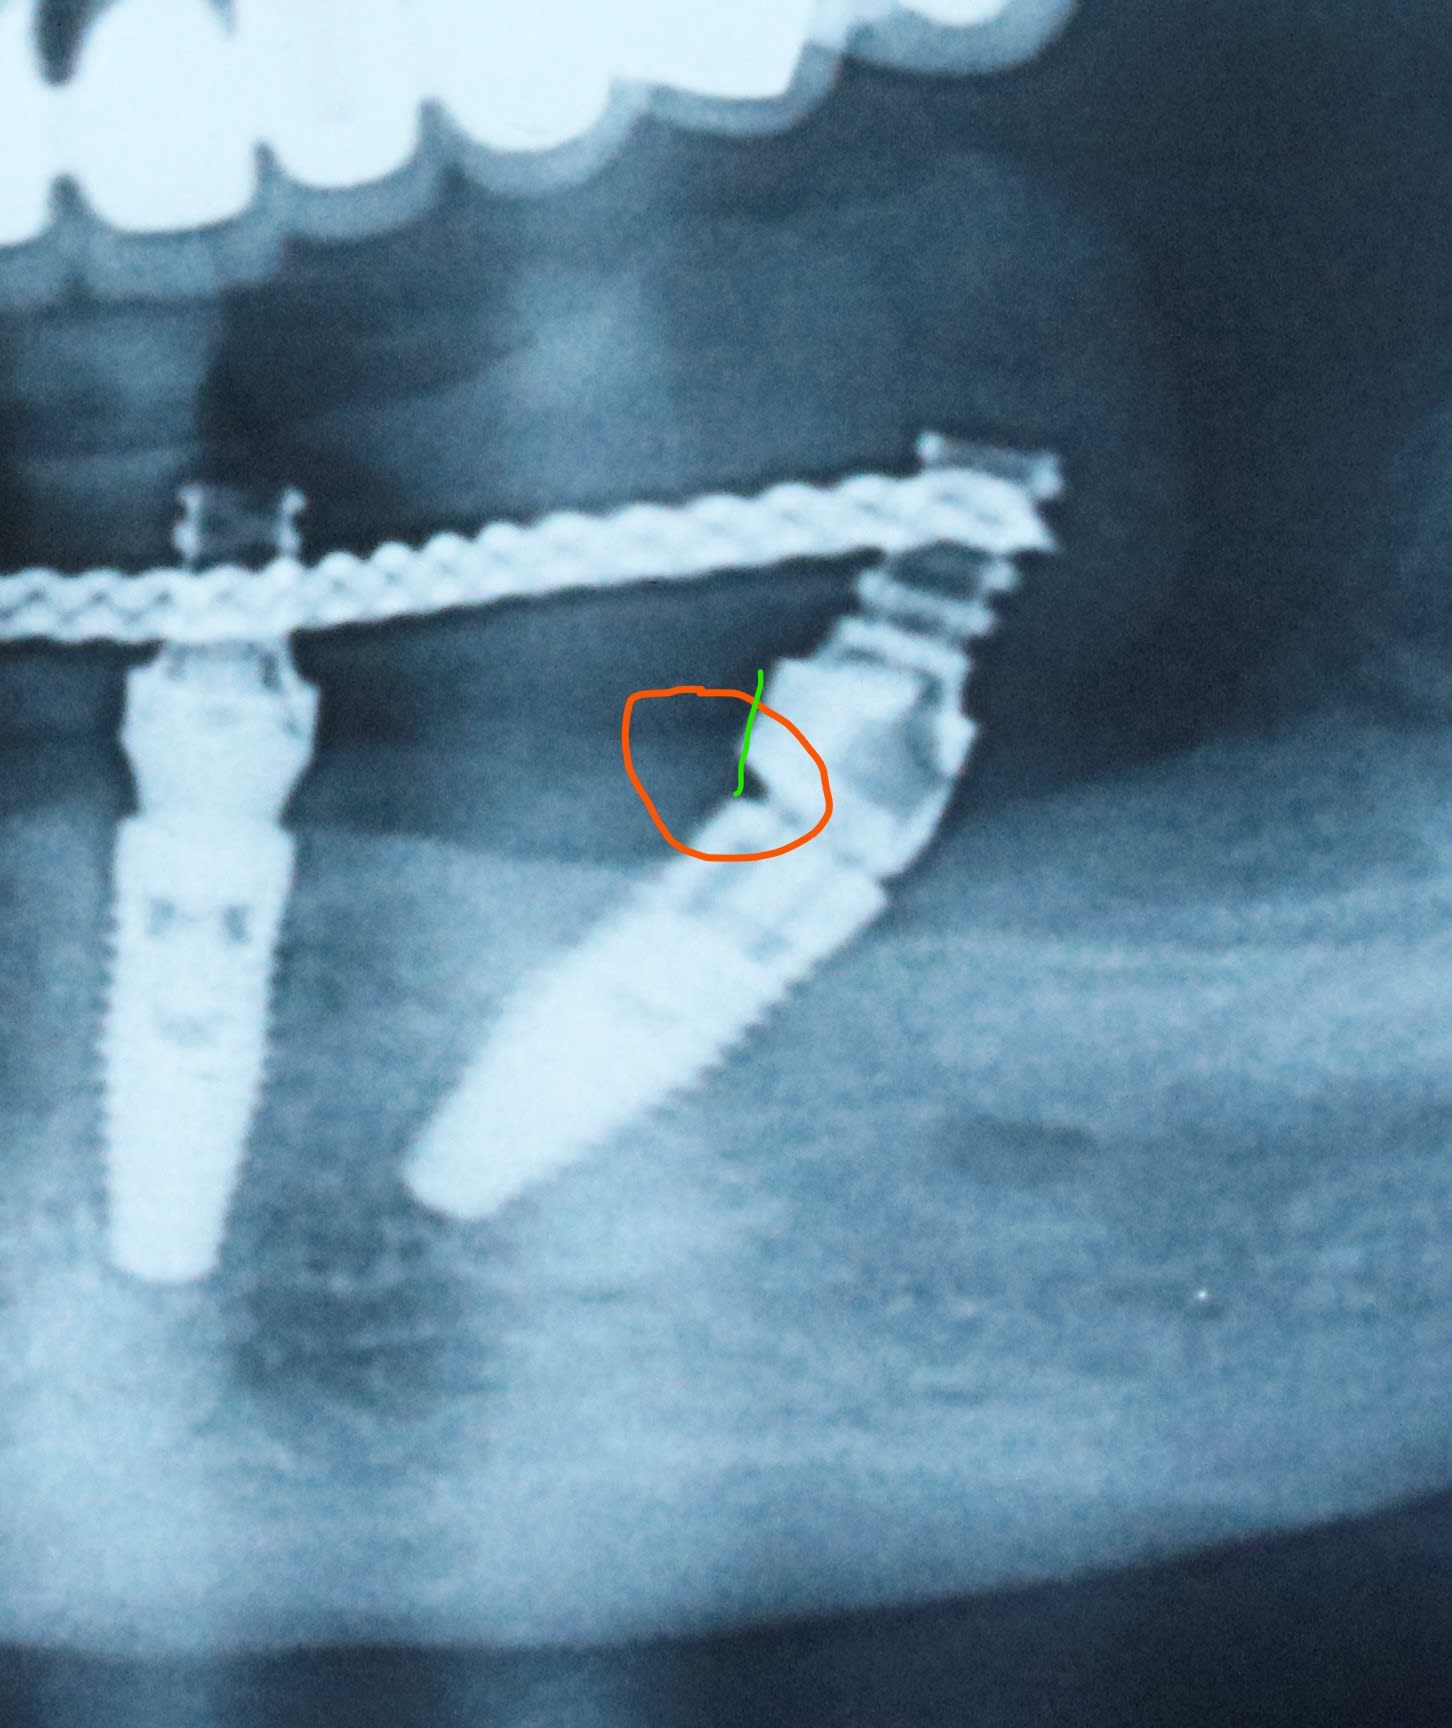

bon , sinon indépendamment de l angulation trop forte , j ai posé plusieurs fois la même question et personne ne m a encore répondu .

quelle est l interet de cet espace ( orange ) ?? , ç est complètement con , non ?

Je pense que si l implant est plus enfoui , le col devient juxta voir infra osseux, ca se joue à pas grand , la base du pilier MUA ne vient pas buter sur l os et donc tu le pose correctement malgré tout ?

S'il y avait un enfouissement normal de l'implant tu verrais cet espace identique sur toute la circonférence du col en switching plate-forme

non . comment veux tu ? ç est des conneries ça .

on le voit bien sur l image de TA2 que c est dissymétrique

La partie haute du multi-unit pour décaler les axes de vissage sur un multi-unit peu anguler mais regarde la partie en contact avec le col de l'implant

si l implant est bien enfouis , l implant a une partie distale sous l os et une partie mesiale en dehors .

ce qui fait que ton plateforme machin qui concerne la gencive n est qu un croissant de lune mesial .

je ne vois pas trop de joint de fibre d etancheité la dedans .